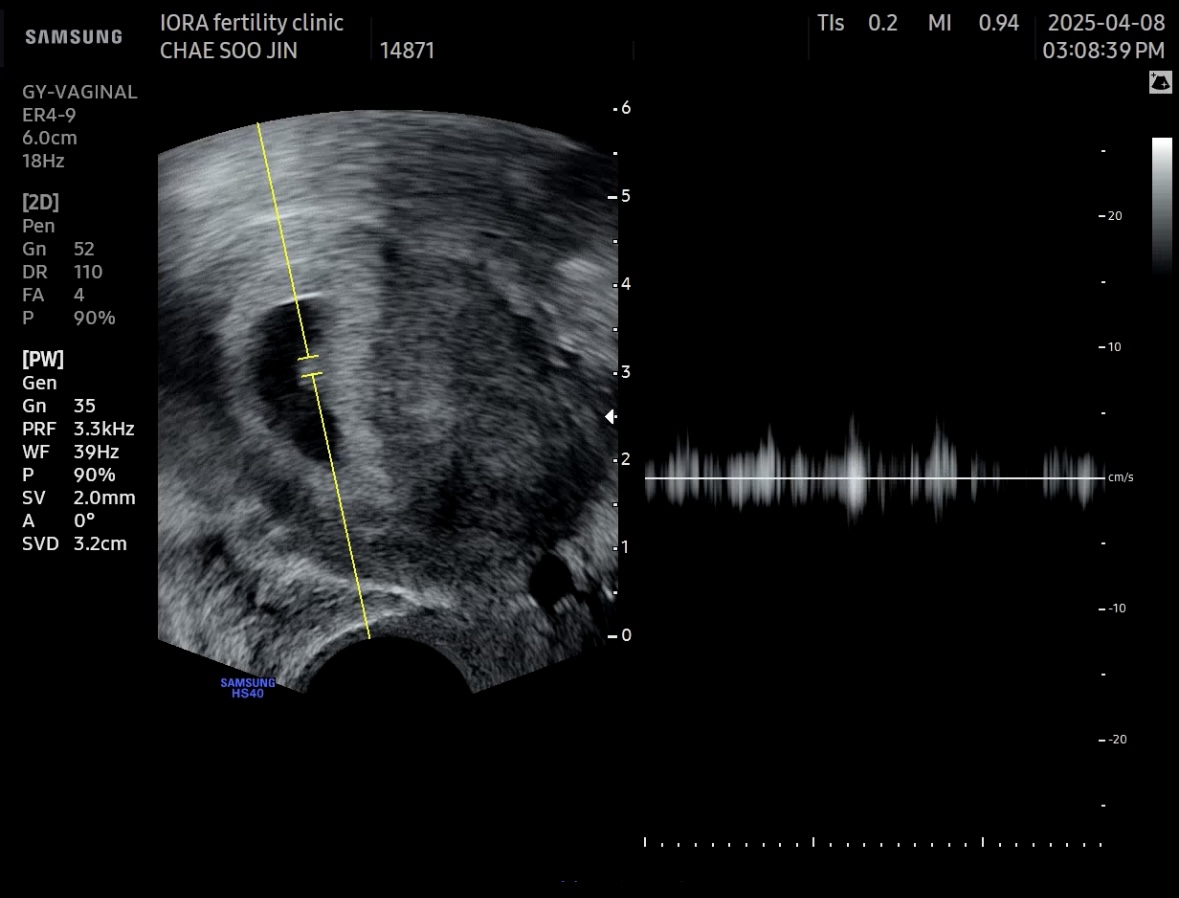

1. 임신 5주 2일. 난황 확인

담당 선생님은 휴진이라 다른 선생님께 진료를 받았는데 초음파상으로는 특별한 이상소견은

확인되지 않았고, 이틀만에 동그랗게 빛나는 난황도 생겼다. 아무래도 착상혈이었나보다.